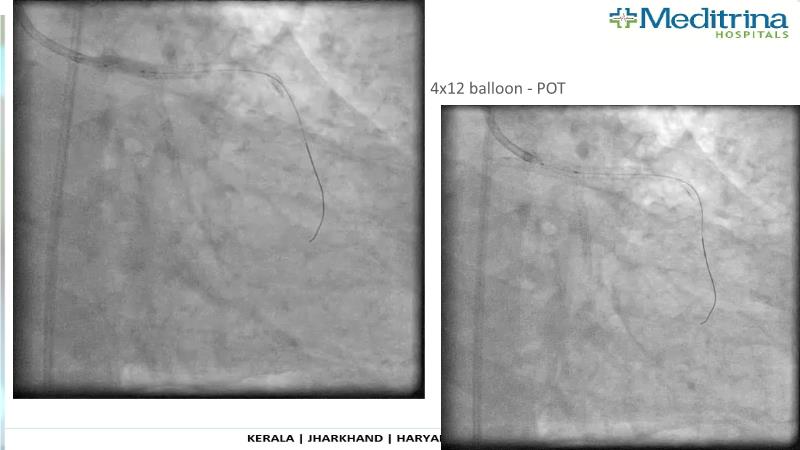

- To define the use of OCT in PCI of complex coronary lesions